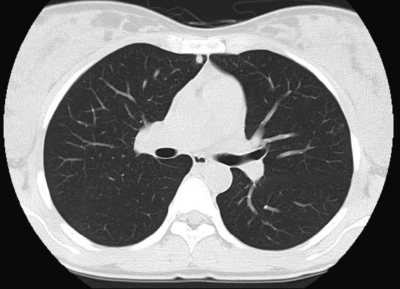

内診で子宮はやや腫大、軟。超音波検査で後壁筋層内に血流豊富な径 1.5 cm の腫瘤を認める。脳、肝、腎臓および腟に異常を認めない。血清 hCG の推移と肺野条件の胸部 CTとを別に示す。